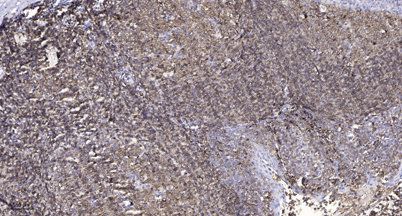

Product name: SR-3A rabbit pAb

Dilutions: Western Blot: 1/500 - 1/2000. Immunohistochemistry: 1/100 - 1/300. Immunofluorescence: 1/200 - 1/1000. ELISA: 1/10000. Not yet tested in other applications.